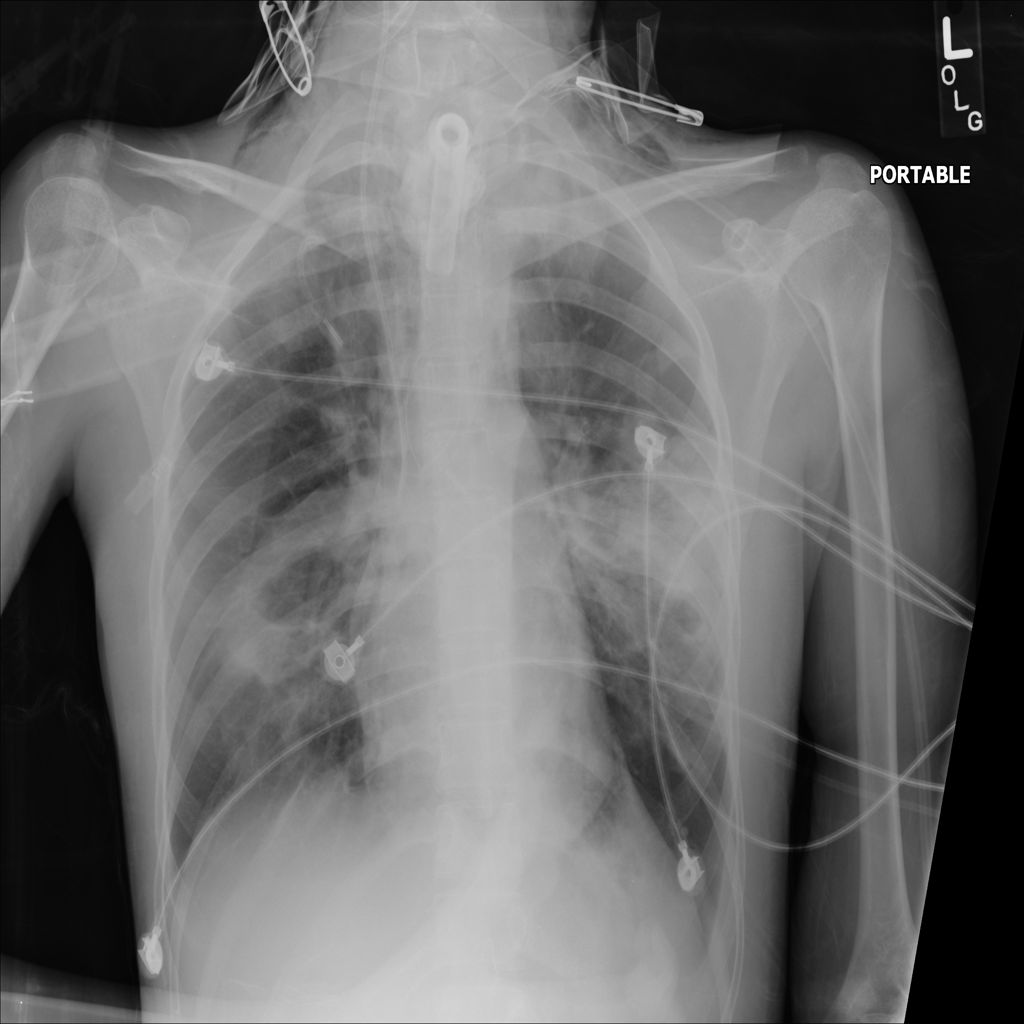

PAT-894B · IMG-000Emphysema

PAT-894B · IMG-000

PA